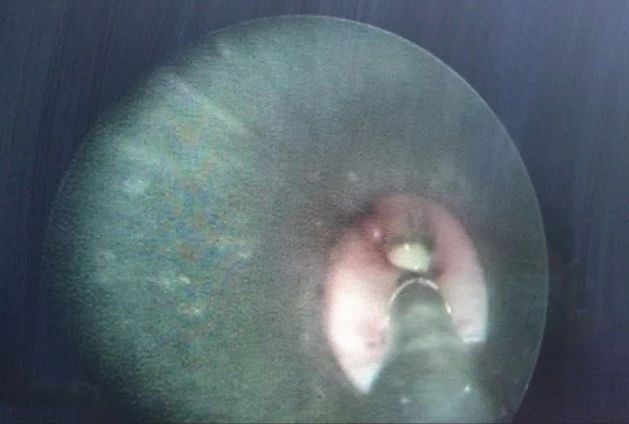

下午接诊一例鼻出血患者,经门诊多次填塞止血后仍有出血,考虑随时有鼻出血加重可能,外科医生与我们协商后决定全麻下为患者行鼻内镜下止血术。患者坐在候诊区,低着头不断地擦拭着吐出的血性液体,家属不安地站在身旁。仔细询问病史,患者告诉我: “出了好多次血了”; “这两天我吃也吃不下,睡也睡不好”; “昨天晚上开始就没吃任何东西了,吃不下”。 看着病人惴惴不安的样子,我只能轻声安慰“会好起来的”。考虑患者清醒合作,咽下血性液体不多,决定行喉罩下全身麻醉。患者入手术室后,心电监护下予面罩吸氧,开放静脉,备好吸引设备,经充分去氮给氧后快速静脉诱导,置入双管喉罩后行控制通气和胃肠减压。手术历时80分钟,喉罩通气良好,清除口腔内残留的血液,充分镇痛下待患者恢复自主呼吸,配合指令动作后拔除喉罩。 本以为这个值班就这样过去了,清晨6点拷机忽然响起,被告知有一例13月龄的小儿气道异物,来不及洗漱我就冲到楼下,准备好药物及紧急气道插管工具。 患儿由父母和爷爷抱到等待室,即使在妈妈的怀里,眼中仍充满了不安。妈妈一边流泪一边诉说着病史,昨天姐姐抱着弟弟玩,爷爷给他们喂板栗,难得回一次老家,大家特别高兴。突然姐弟俩摔了一跤,弟弟含着一嘴的板栗哇哇大哭,妈妈赶紧跑过去抠出儿子口中的板栗,但孩子仍然被呛得不停地咳嗽,午后孩子不但频繁咳嗽,还喘得厉害。家长带着他一路从当地县中心医院、市医院辗转到上海儿童医院,最后凌晨3点赶到我们医院。 (患儿术前CT片) 患儿近期患幼儿急疹已愈,既往有湿疹史,对多种食物过敏,听诊右上肺无呼吸音,左肺稍许哮鸣音,我们讨论后决定保留呼吸下经支气管镜行气道异物取出术。二线医生把患儿抱入手术室坐在怀里,吸着麻醉药慢慢入睡,开放静脉后我们使用静脉药物成功保留住了自主呼吸,整个手术过程中,患儿自主呼吸平稳,氧供充分,为外科医生提供了良好的手术条件。其实,板栗这样的气道异物,对外科医生来说难度颇大,钳子一夹“泡软的”板栗就碎了,非常难取,但是在主刀医生的不懈努力下还是把堵塞的气道清理干净了。 (异物——“泡软”的板栗) 术后我们置入了一枚双管喉罩,等待患儿苏醒。这时接班医生来了,由于气道异物患儿的苏醒期仍有发生突发事件的风险,我们不放心走,四个麻醉医生一起围坐在孩子身边。看着他睁开眼睛找妈妈,我们悬着的一颗心也放了下来。